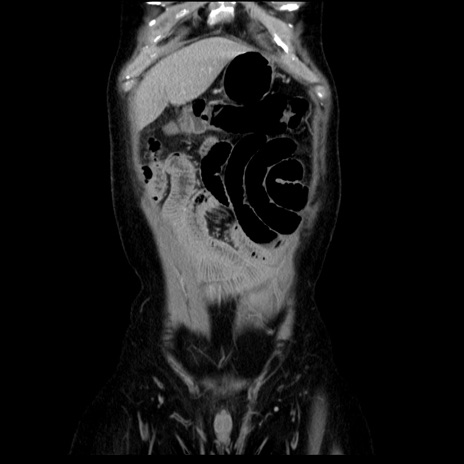

横断像

【症例】40歳代男性

【現病歴】2日前から胃痛あり。徐々に周期的な激痛に変化した。本日になっても激痛があるため受診。

【身体所見】意識清明、BT 38-39℃台あり、腹部:膨満、やや硬、右下腹部に圧痛あり。

【データ】WBC 8500、CRP 23.26